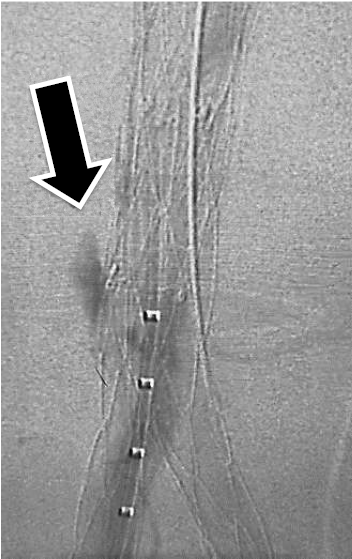

Qual o tipo de endoleak se observa na imagem abaixo?

Fonte: Banca Examinadora, 2026.